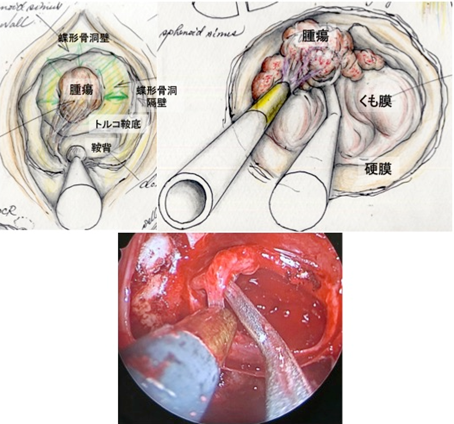

[3]経鼻的経蝶形骨洞的腫瘍摘出術

当院では耳鼻科と協力して片方の鼻孔から腫瘍の摘出を行う「経鼻的経蝶形骨洞的下垂体腫瘍摘出術」で手術を行っております。この摘出法は従来の上口唇の裏側の歯肉部を切開する方法に比べ、術後に口腔・鼻腔内の違和感が少ないという利点があります。

この手術は、鼻腔という極めて限られた空間の中で脳深部の操作を行うために、脳神経外科の手術の中でも極めて特殊な方法です。この手術では従来手術用顕微鏡を使用していましたが、2013年からは当院耳鼻科医と協同で硬性内視鏡単独手術により下垂体腫瘍摘出術を行っています。これは内視鏡を使用することにより手術顕微鏡では死角となる部位の腫瘍摘出率を向上することができます。

下垂体腺腫内視鏡単独経鼻的アプローチ

下垂体腺腫に対して内視鏡単独で経鼻的アプローチにより摘出術を施行。耳鼻科医と合同で行っている。(左)術中および術後MRIの所見。腫瘍被膜上に造影病変が認められているが、術後MRIでは消失している。術中MRI画像をナビゲーション用にアップデートし、残存腫瘍の摘出操作の際に役立てている。